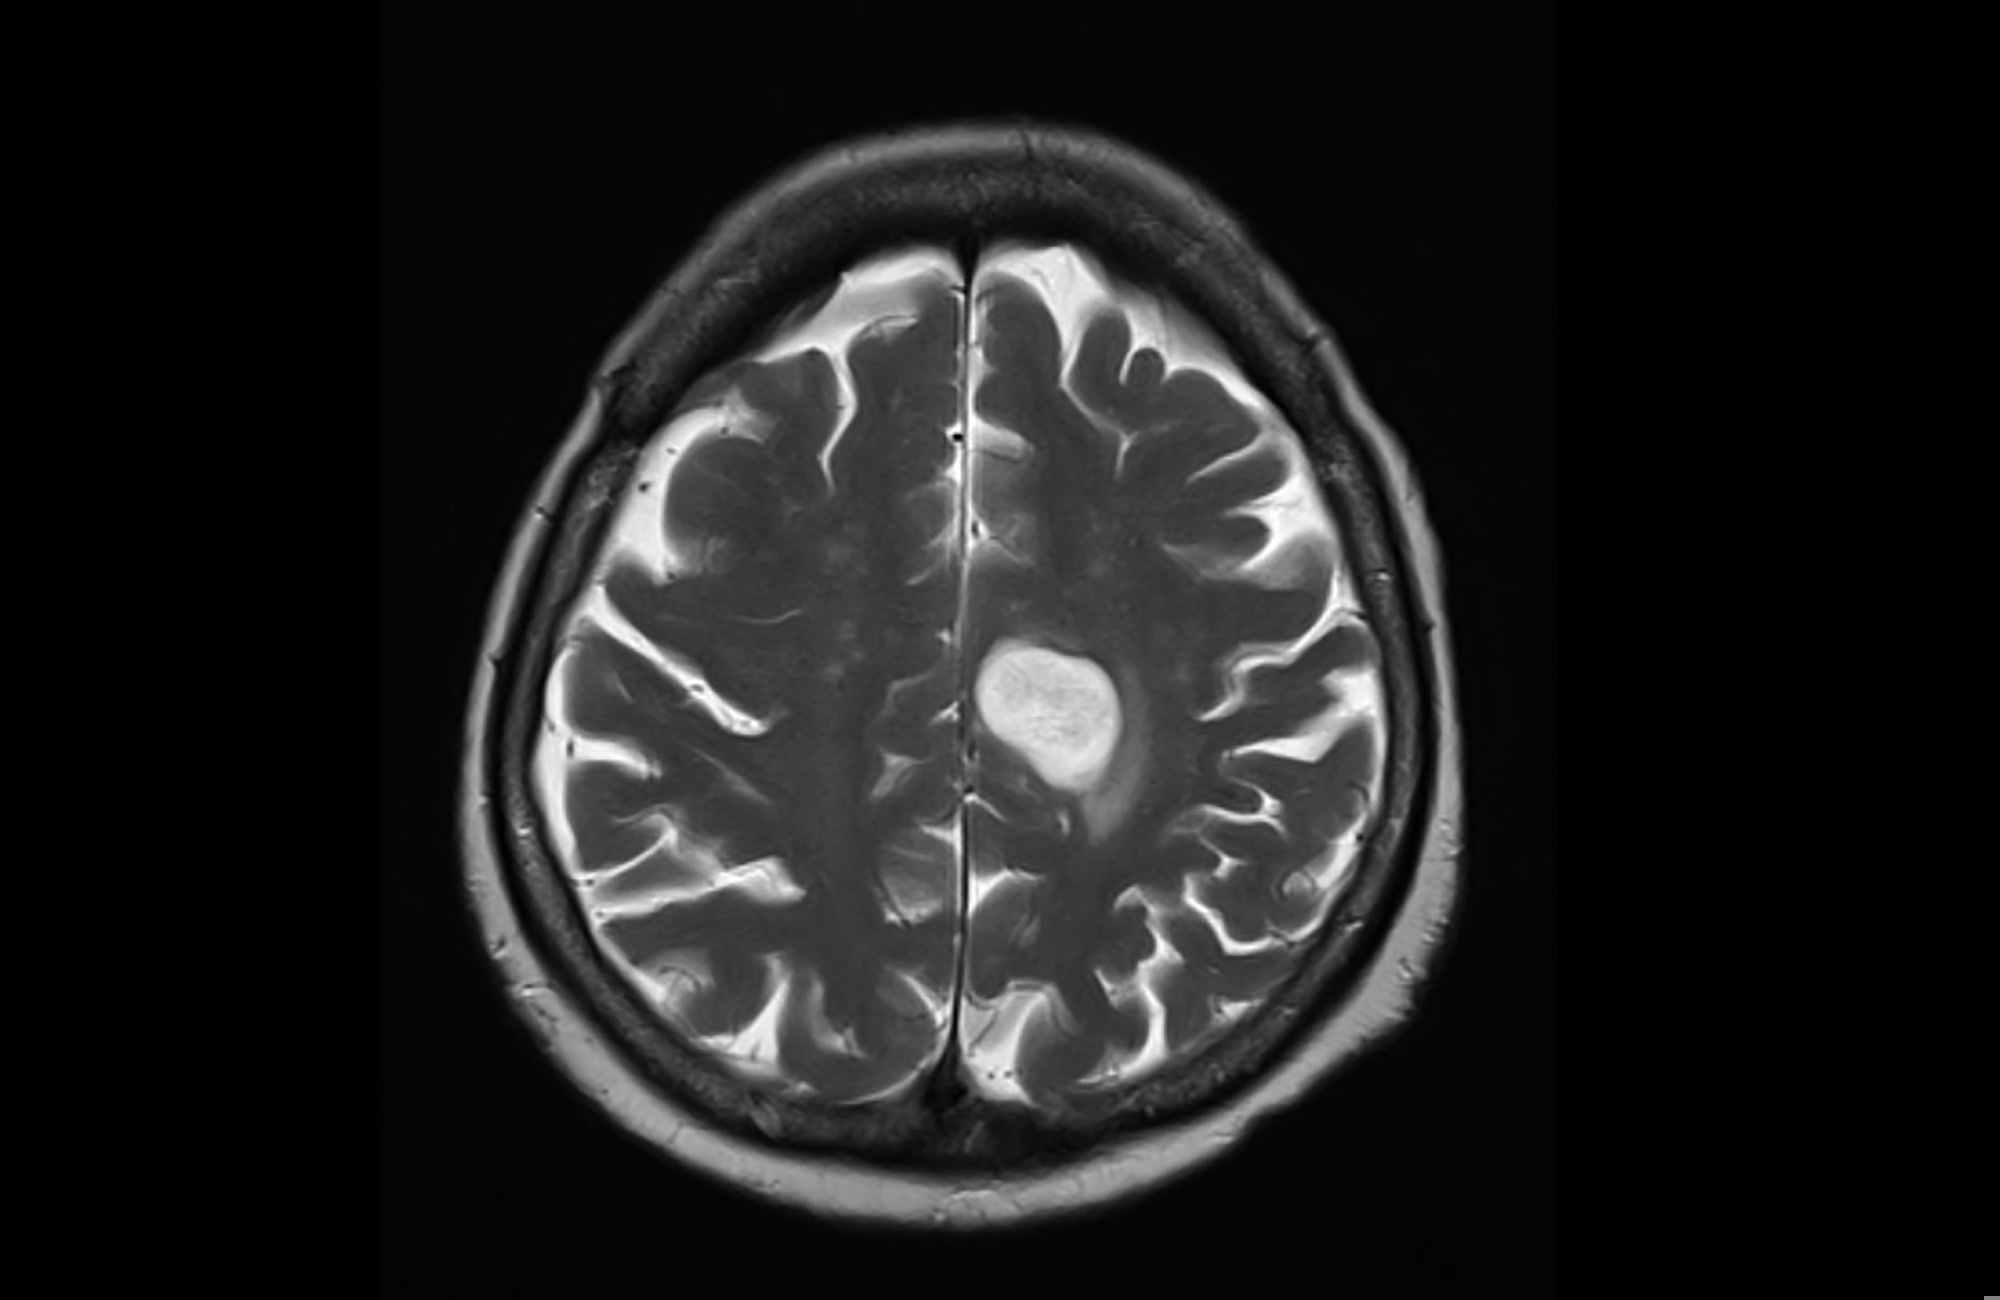

Study: Glioma mutational signatures associated with haloalkane exposure are enriched in firefighters. Image Credit: Yok_onepiece / Shutterstock.com Study: Glioma mutational signatures associated with haloalkane exposure are enriched in firefighters. Image Credit: Yok_onepiece / Shutterstock.com

A glioma is a type of brain tumor that arises from glial cells. Based on their aggressiveness, gliomas can be further classified into four grades, with grades I and II considered to be less invasive than grades III and IV.